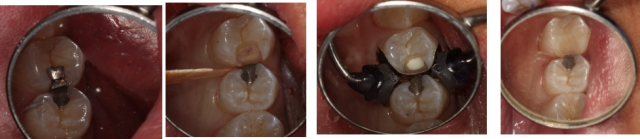

When caries are in close proximity to the pulp, an indirect pulp cap can be performed. In this procedure, much of the infected and affected dentin is removed without exposing the pulp in a vital, healthy tooth. This is followed by the placement of a medicament such as calcium hydroxide or a bioactive material to promote the formation of tertiary dentin.1

This procedure removes all carious enamel but leaves carious dentin in place adjacent to the pulp chamber. A medicament is placed over the remaining caries, a provisional restoration is placed, and the patient is scheduled for a second appointment. At the second visit, the provisional restoration and remaining caries are removed and a definitive restoration is placed.

The goal of a stepwise approach is to promote the formation of tertiary dentin and to change the environment within the tooth to prevent further progression of the carious lesion.2

With a single-visit indirect pulp cap, as much of the carious lesion as possible is removed without inducing a pulpal exposure. A medicament is placed in the deepest aspect of the preparation, and a definitive restoration is placed. Unlike the stepwise approach, a single-visit excavation does not require a second visit to restore the tooth, and there is no risk of an inadvertent pulpal exposure when re-entry of the tooth occurs.3,4